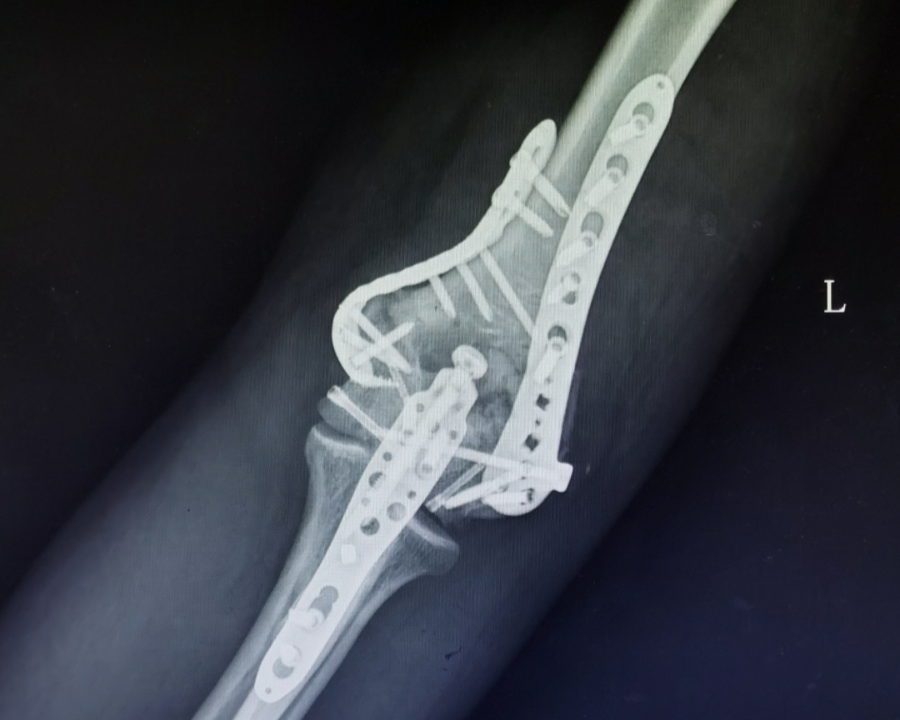

儿童肱骨远端粉碎性骨折治疗 [病例帖]

【经典病例】灵活而牢靠,力达康肘关节假体治疗高龄"肱骨远端粉碎性

肱骨远端粉碎性骨折怎么办?

肱骨远端骨折骨合成的矢量图

一例肱骨远端骨折aob23